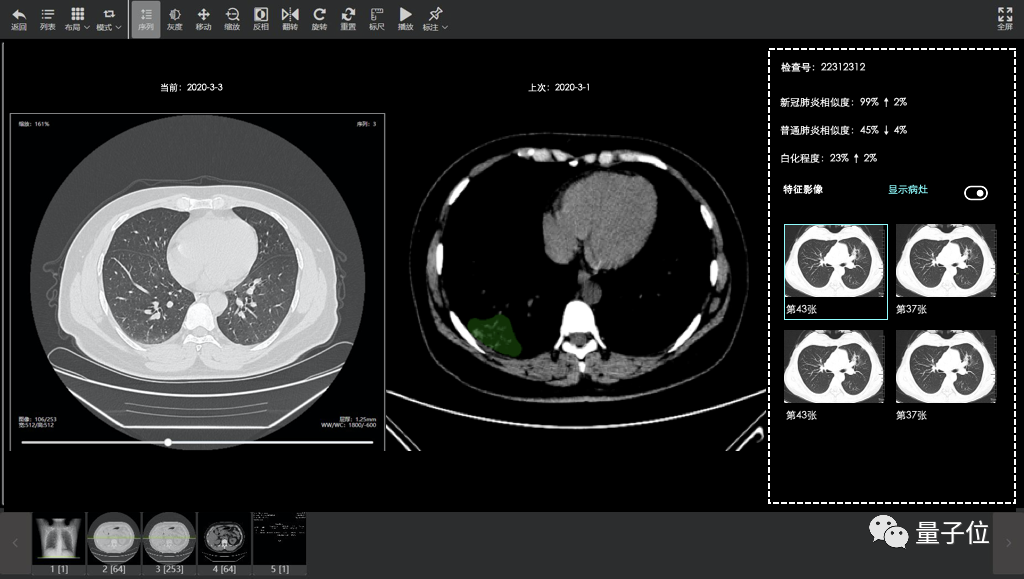

2月15日,达摩院医疗AI团队与合作伙伴一起,基于5000CT影像样本数据,快速研发出了CT影像算法,在郑州小汤山上线,可以在20秒内对新冠疑似患者CT影像做出判读,并量化病症的轻重程度,分析结果准确率达到96%。

至今这套AI系统已在浙江、河南、湖北、上海、广东、江苏、安徽等16个省市的170家医院落地,诊断超过34万临床病例。

2月5日,国家卫健委公布的诊疗方案第五版中,正式将CT 影像临床诊断结果作为新冠肺炎病例判断的标准之一。

虽然这直接加快了新冠肺炎疑似病例的确诊速度与准确度,但对于前线医生来说,却是不小的负担。

一位新冠肺炎病人的 CT 影像大概在300张左右,每诊断一个病例,影像医生需要投入大约为5-15分钟时间。一名医生每天连续不间断工作12个小时,只能诊断大概72个病例。

当时——2月4日晚,全国一共有疑似病例23260例,追踪到(新冠肺炎患者)密切接触者252154人……提升临床诊断效率,成为抗疫期间核心需求之一。

而达摩院等医疗AI机构,就在这样的险峻形势中出手,联合伙伴打造的新冠病毒CT影响诊断系统,从上传数据到得到结果,诊断一个病例平均仅需20秒,计算时间最快仅2秒。

虽然仍旧需要医生进一步配合才能够得到更准确诊断结果,但对效率的提升, 无疑是巨大的。这也是医疗AI能够在抗疫期间得到推广的原因之一。